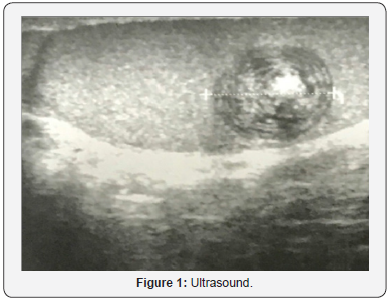

A 28-year-old male patient, with no medical history, consulted for primary infertility after 3 years of marriage. His physical examination showed a hard swelling on the left testicle surface, suggesting the presence of a mass, without neither pain nor inflammatory signs. The contralateral testicle was normal. The patient does not report the presence of LUTS (lower urinary tract symptoms) or other associated signs, and in particular, tuberculosis signs. Two spermograms performed one month apart showed oligoasthenoteratospermia (OATS). The measurement of tumor markers was normal.Ultrasound showed a rounded, intra-parenchymal formation with a heterogeneous and hyperechogenic center, associated with peripheral calcifications (Figure 1). No anomaly was objectified in the contralateral testicle.Given the ultrasound appearance of the testicular lesion, conservative surgery has been proposed to the patient. Thus, exploration by left inguinal incision was performed with first clamping of the spermatic cord (Figure 2).

Ultrasound shows a characteristic image of the TEC, a “target” image. The cystic wall can be either hypoechoic or hyperechoic due to focal calcifications. The center of the cyst is heterogeneous with hyper or hypoechoic zones attributable to the density of the keratin lamellae that compose it [5-7]. Since the advent of MRI, the images are more characteristic of the TEC, which makes it possible to differentiate from other solid intratesticular lesions. The typical appearance is the “bull’s eye”. The wall and the centre of the cyst are in hypo-signal in T1 and T2 weighting. Between these two zones, there is in T1 and T2 weighting a hyper-signal that corresponds to isolated and degenerated epithelial cells (rich in water and fat) [6]. There is no enhancement of the signal after injection of contrast dye because it is an avascular structure.